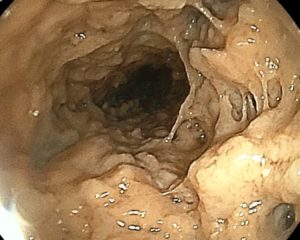

こちらの写真は、免疫機能が低下した人の食道カンジダ症です。

白いふわふわした部分がすべて「カンジダ」の繁殖です。

飲み込みにくさや胸の痛みなどの症状が出てきます。

この様な場合は、食道カンジダ症の治療やその原因精査が必要となります。